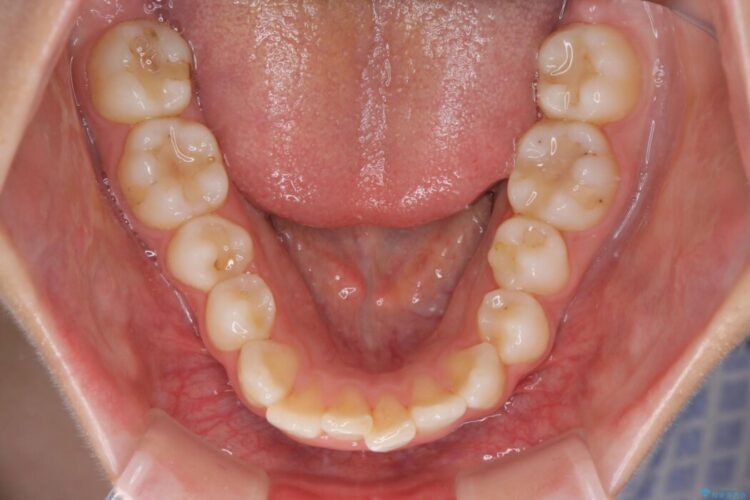

上下顎の歯列のガタつきを治したいとのことで来院されました。

全体的に少し内側へ傾斜しているのが確認できました。そのため歯列弓が狭まり噛み合わせにも影響しています。

まずは奥歯を後ろへ遠心移動をさせながらがたつきを改善していくマウスピース矯正をご提案しました。